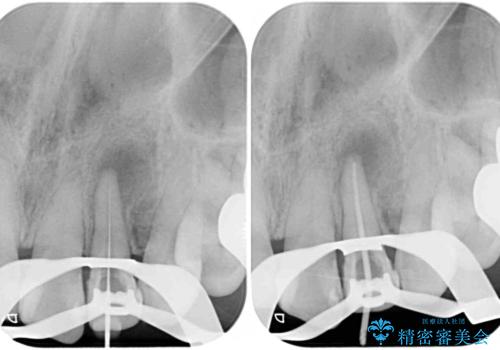

レントゲン写真から、大きくなった根尖病変が認められました。

根管治療後速やかに痛みが消退し、6ヶ月後のレントゲン写真では、根尖部の病変がほぼなくなっていることが分かりました。